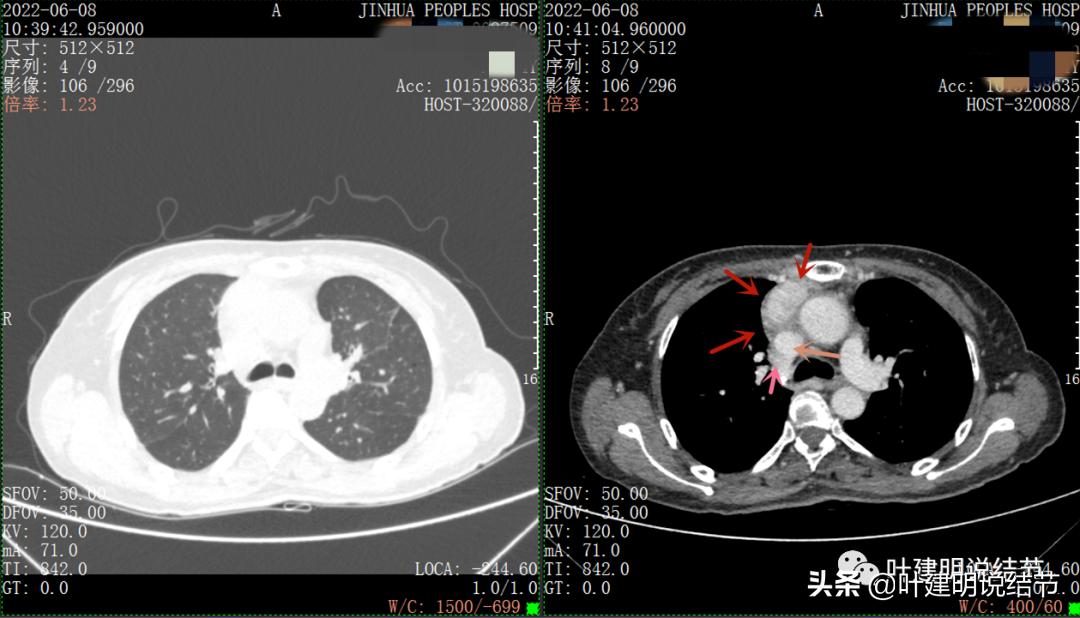

以下图片左侧是肺窗,右侧是纵隔窗。红色箭头示病灶,桔色箭头示无名静脉,黄色箭头示支气管,砖色箭头示上腔静脉,蓝色箭头示主动脉,紫色箭头示肺动脉。

病灶纵隔胸膜侧非常光滑,说明来源于纵隔

粉色箭头示淋巴结可能